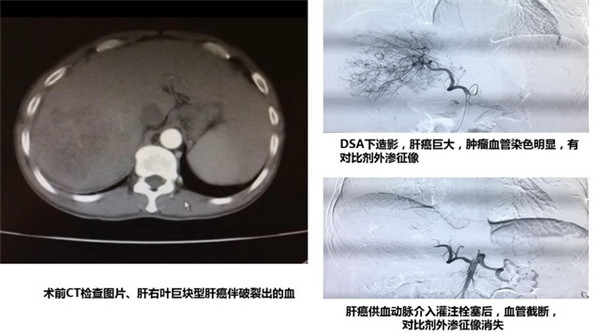

当天的一件意外事件也成了本次活动的又一个亮点,将一附院前来交流的目的落到了实处。就在一附院专家走访防城港市中医医院病房,针对疑难危重患者进行多学科联合会诊时,消化科恰巧新收入一名急性腹痛患者,结合紧急CT检查结果和既往病史,明确诊断为肝右叶巨块型肝癌伴肝包膜下破裂出血,有“肝动脉造影和介入灌注栓塞术”指证,建议立即行急诊介入手术,以抢救患者生命。然而该医院之前尚未开展过肝癌介入手术。经与患者家属沟通同意后,一附院介入科罗耀昌主任和何海源医师临危受命,仅用了45分钟顺利在该院完成了肝癌破裂出血的急诊介入手术,患者生命得到了及时挽救。这成为防城港市中医院第一台肝癌介入手术。此事件也成为实现一附院与中医药发展医联体单位合作、发展、共赢目标的具体体现,共同为患者健康造福。

一附院介入科罗耀昌主任在防城港市中医医院手术室顺利完成手术